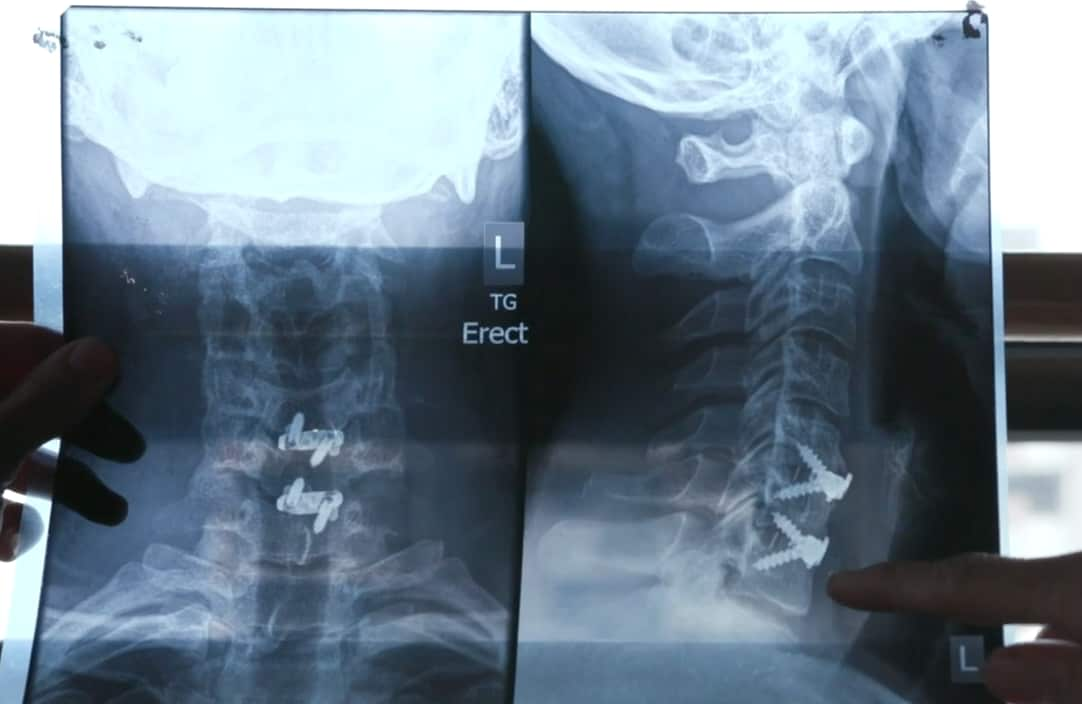

Scans showed Daniel had seven injured spinal discs, as well as nerve damage, a torn bicep and osteoarthritis.

Cirque du Soleil paid for Daniel's first lumbar spinal surgery in 2017 and some associated rehab, but that was it.

He says he has since had at least seven operations and procedures for his spine as well as continuous rehab, most of which he's paid for himself.